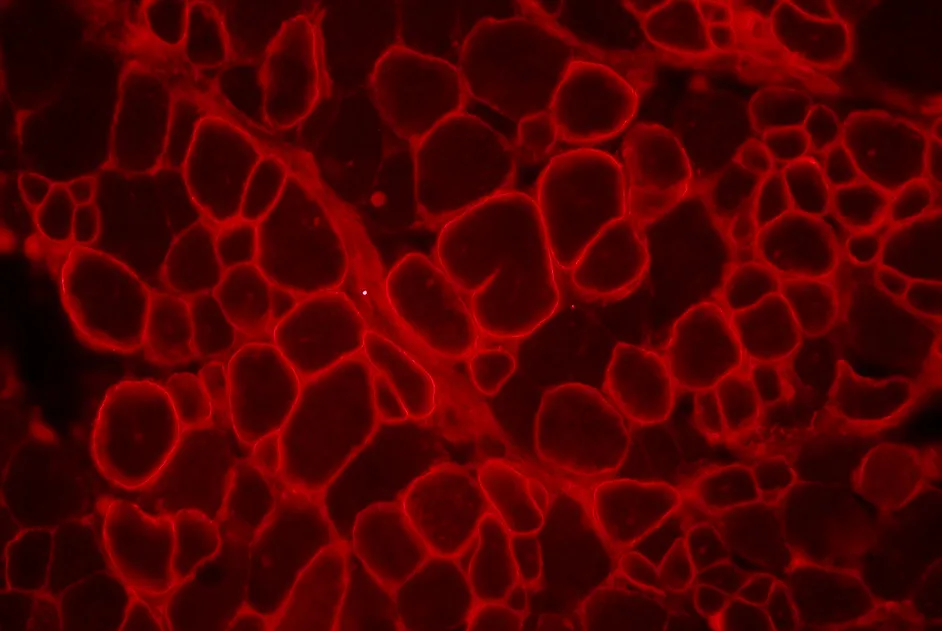

Myopathies centronuléaires : un 7e atelier ENMC

Le compte rendu du 198e workshop ENMC, correspondant au 7e atelier exclusivement consacré aux myopathies centronucléaires, est paru en août 2013.